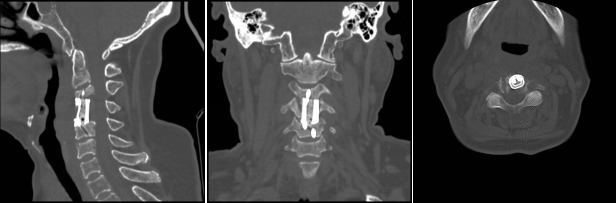

術(shù)后影像學(xué)顯示,植入內(nèi)植物位置滿意,與終板匹配性良好,穩(wěn)定性佳。術(shù)后患者生命體征平穩(wěn),癥狀明顯緩解,活動良好,目前已出院。

通訊員殷君發(fā)報道:近日,衡陽市中心醫(yī)院脊柱外科蘇光輝主任團隊順利完成一例高難度頸椎骨質(zhì)破壞病灶切除+3D打印一體式椎體植入重建手術(shù),術(shù)后影像學(xué)顯示,植入內(nèi)植物位置滿意,與終板匹配性良好,穩(wěn)定性佳。術(shù)后患者生命體征平穩(wěn),癥狀明顯緩解,活動良好,目前已出院。此手術(shù)的圓滿成功是衡陽市中心醫(yī)院3D打印技術(shù)臨床應(yīng)用領(lǐng)域取得的又一重要突破,是湘南地區(qū)乃至全省首例疑難病癥的創(chuàng)新舉措,標(biāo)志著脊柱外科手術(shù)開始邁向個性化、精準(zhǔn)化。